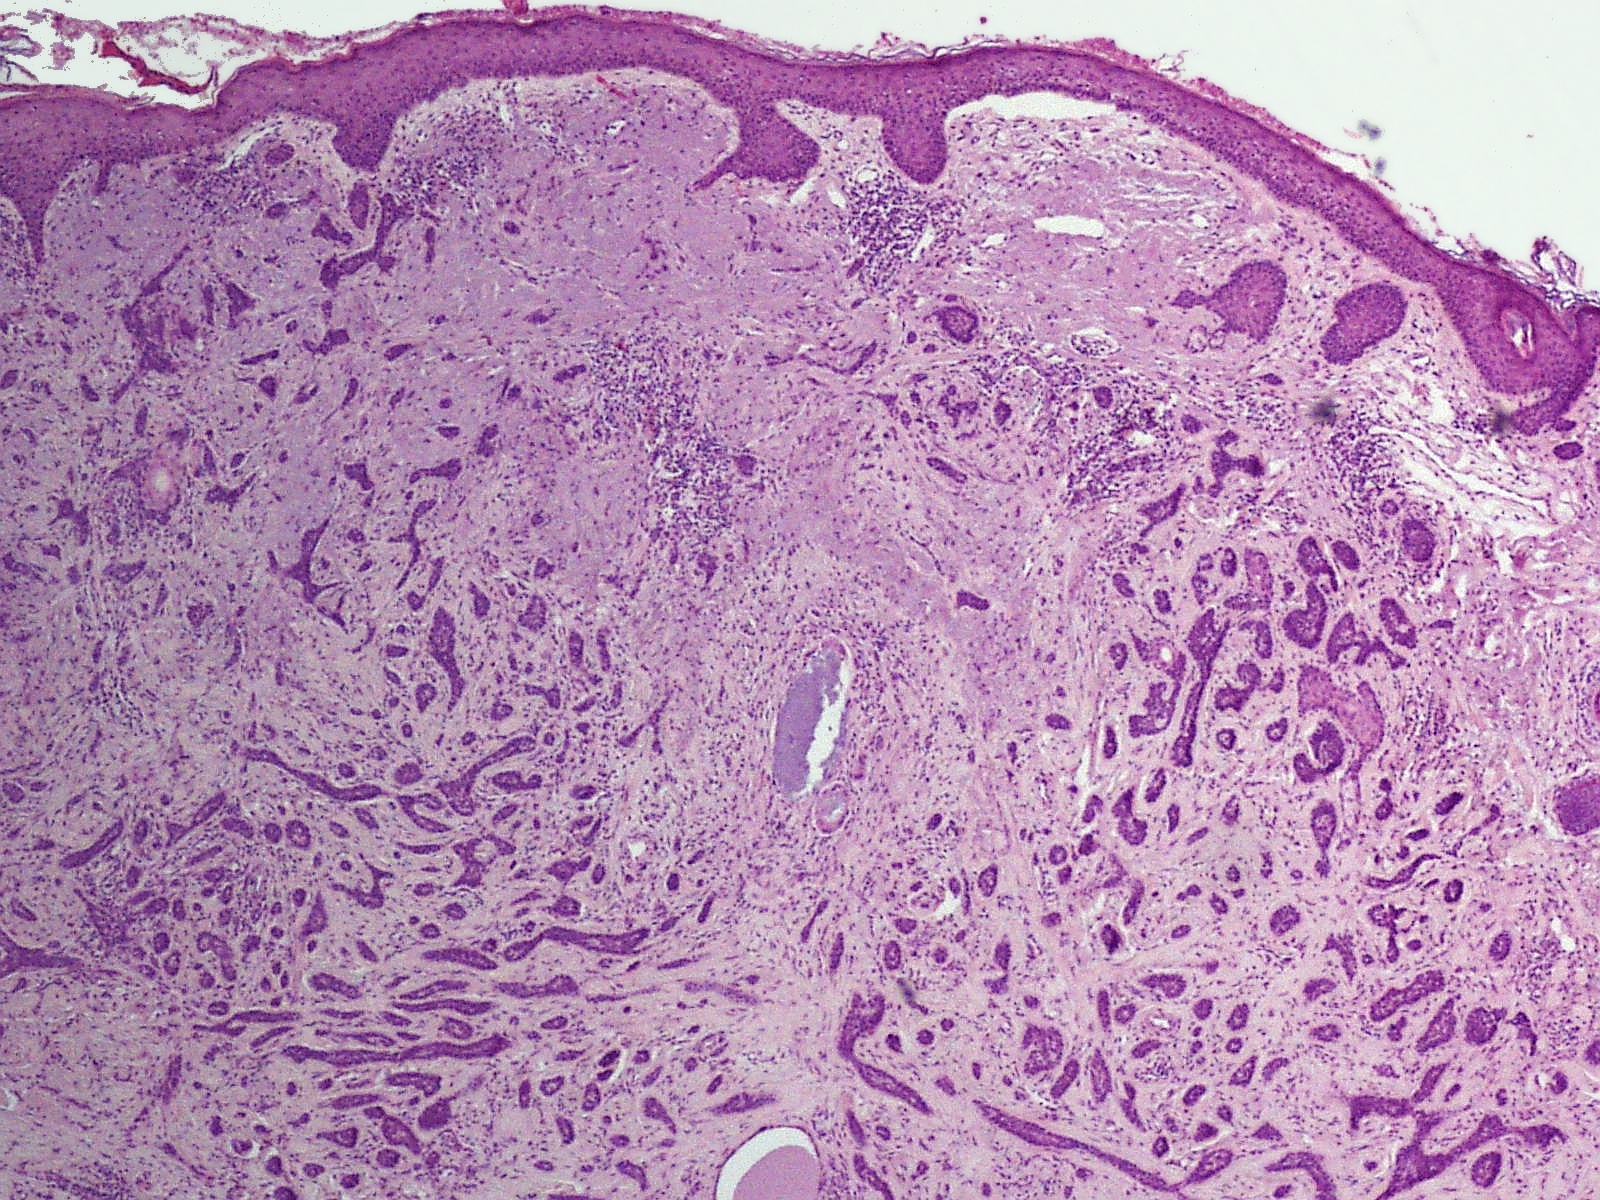

Groeiwijzen (histologische

varianten):Naast klinische varianten worden er ook histologische

varianten onderscheiden. Binnen 1 laesie kunnen verschillende groeiwijzen gecombineerd

voorkomen, een biopt kan niet representatief zijn voor de hele laesie. Sprieterige

en micronodulaire BCC's zijn agressiever dan compacte of superficiële BCC's.

| 1. |

compact basaalcelcarcinoom (solide, nodulair). Er zijn grote

nesten met duidelijke begrenzing naar het omgevende niet-aangedane

weefsel. De stromareactie is vaak beperkt. |

| 2. |

superficieel basaalcelcarcinoom, zeer oppervlakkige nesten,

vaak multifocaal. |

| 3. |

sprieterig basaalcelcarcinoom, kleine strengetjes van basaloïde

cellen omgeven door desmoplastisch stroma, de begrenzing naar het

omgevende weefsel is vaak onscherp. |

| 4. |

micronodulair basaalcelcarcinoom, groeiend in kleine, fraai

afgeronde nesten elk ongeveer ter grootte van de bulbus van een

haarfollikel. |